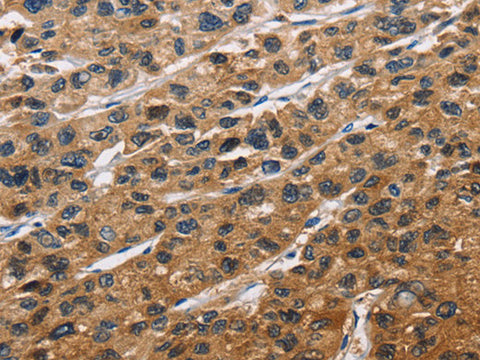

EIF4EBP2 Polyclonal Antibody Store at -20°C

Applications IHC

IHC 1:50-1:200